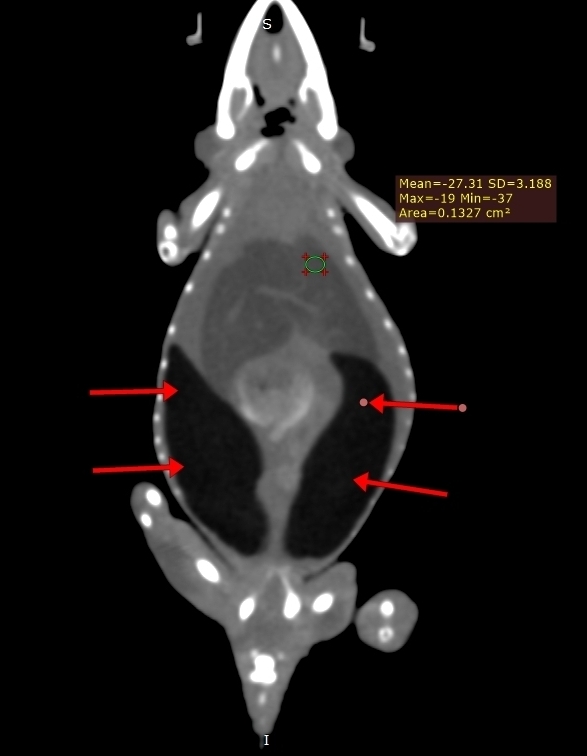

Компьютерная томография на сегодняшний день представляет собой наиболее информативный метод визуализации для диагностики липидоза печени у пресмыкающихся, включая ящериц2,12,13,19. Данный метод позволяет количественно измерять рентгенологическую плотность в единицах Хаунсфилда (HU), основываясь на поглощении рентгеновских лучей различными тканями8. Плотность печени менее 20 HU коррелирует с наличием умеренного липидоза печени у бородатых агам и других видов ящериц2,7 (фото 1-3) . Компьютерная томография оказалась высокоточным методом диагностики липидоза печени у бородатых агам как с умеренной, так и тяжелой степенью заболевания. Была выявлена линейная корреляция между плотностью печени, измеренной в единицах Хаунсфилда, и результатами гистологического анализа образцов печени. Увеличение содержания жира в печени на 10% соответствовало уменьшению плотности печени на 4 HU2.